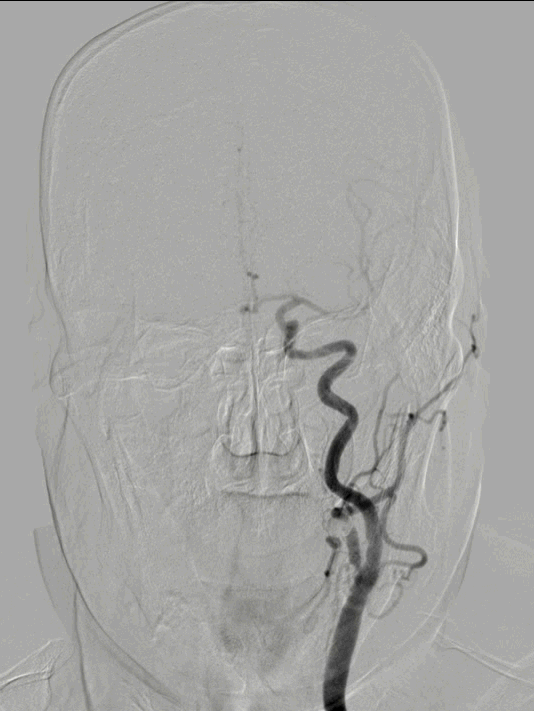

FlowGate 2同轴Catalyst 7、Synchro 2多次调整后穿过C1起始闭塞处,MicroPort Pioneer 2.5mm×20mm球囊C1起始处缓慢扩张,顺球囊Catalyst 7穿过闭塞段,继续向前推进FlowGate 2失败, Catalyst 7 C1抽吸出长条血栓。

Catalyst 7 C1抽吸出大负荷血栓。

Catalyst 7再次通过闭塞处于C2-C4近端抽吸,再无血栓抽出,球囊辅助通过(BTA)技术无法将CAT7带入C4远端,CAT减容任务完成,使用Solitaire FR 6×30支架行完整BADDASS技术, 6×30支架前行张力非常大,释放时并无法顺利推出Rebar 18微导管,导致支架释放略近于预期位置。

BADDASS技术下支架取出长条血栓,3D-DSA可见眼动脉下方重度狭窄,CAT 7在张力下的上行切割狭窄处,导致小夹层产生。

术后RICA造影 :mTICI 3级。